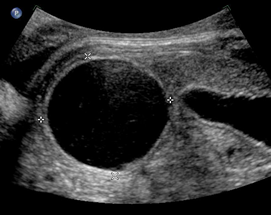

Above. Case 3. 28 3/7 weeks gestation. Transverse view of a cyst in the right upper quadrant.

Above. Case 3. 28 3/7 weeks gestation. Longitudinal view of a cyst in the right upper quadrant. Note the close proximity of the cyst to the fetal spine. On MRI, the kidney is displaced inferiorly and given the potential retroperitoneal location, a duplication cyst of the gastrointestinal tract is a possibility.